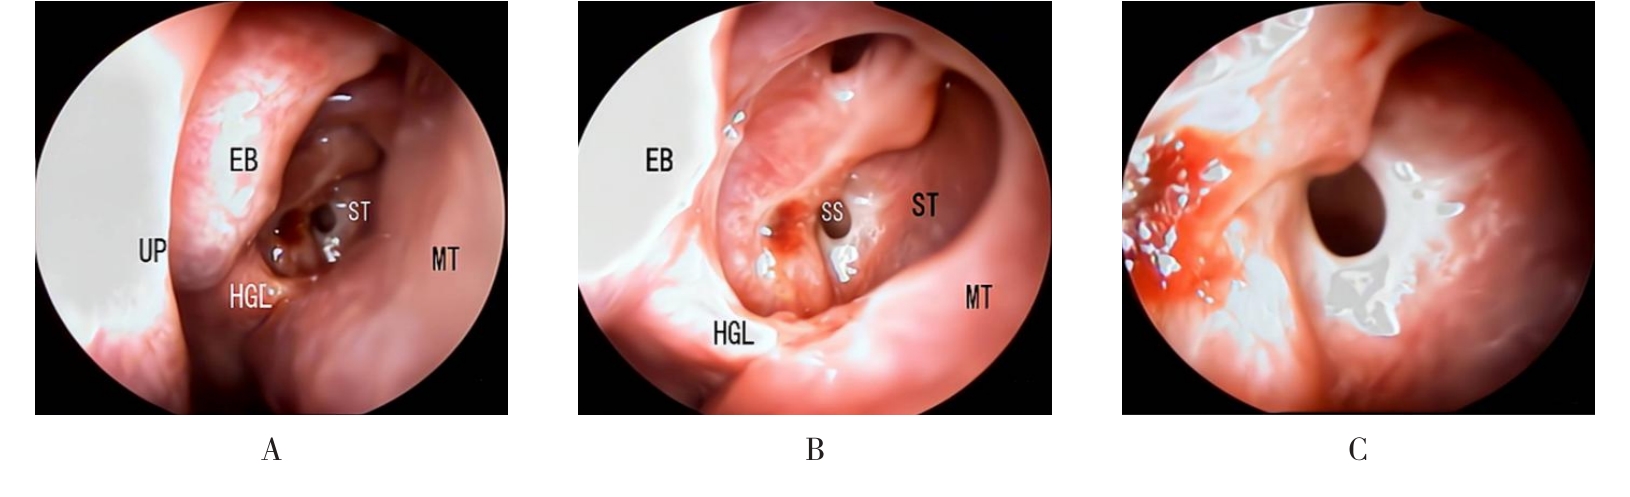

• 内镜下经中鼻甲基板入路四步程序化开放蝶窦的疗效分析

摘要:目的 探究经中鼻甲基板入路的手术技巧及临床效果,旨在系统评估一种兼具良好手术视野和微创性的蝶窦开放径路。方法 回顾性分析2019年9月-2023年9月该院收治的35例孤立性蝶窦病变或单侧蝶窦伴毗邻筛窦受累患者的临床资料,均经中鼻甲基板入路的“四步”程序化操作开放蝶窦。观察手术相关情况和并发症发生情况;采用视觉模拟评分法(VAS)评分,评估头痛和流涕等症状改善情况;采用改良隆德-肯尼迪(MLK)评分,评价术腔恢复状况。结果 所有患者术中保留钩突、中鼻甲和筛泡,26例(74.3%)保留上鼻甲;所有患者均达到临床治愈标准,表现为:术腔引流通畅,黏膜完全上皮化,以及蝶窦开口维持良好开放状态。术后病理显示:蝶窦霉菌病19例(54.3%),蝶窦息肉7例(20.0%),蝶窦黏膜慢性炎症9例(25.7%)。所有患者均未发生严重并发症,仅1例(2.9%)于术后12 d出现中鼻甲创面渗血,经电凝止血后治愈。头痛VAS评分由术前的(4.71±1.66)分,降至术后的(0.83±0.39)分,手术前后比较,差异有统计学意义(t = 13.71,P < 0.01);流涕VAS评分由术前的4.00(0.00,6.00)分,降至术后的0.00(0.00,1.00)分,手术前后比较,差异有统计学意义(Z = -4.47,P < 0.01);手术前后嗅觉减退VAS评分比较,差异无统计学意义(P > 0.05)。MLK评分由术前的4.50(2.00,4.00)分降至1.00(0.00,1.00)分,手术前后比较,差异有统计学意义(Z = -5.20,P < 0.01)。结论 经中鼻甲基板入路蝶窦开放术,严格遵循鼻窦解剖层次,在最大限度地保留鼻腔生理结构的前提下,可获得理想的术野暴露。该术式对于局限于蝶窦及后组筛窦的病变,具有确切的临床疗效。值得应用于临床。